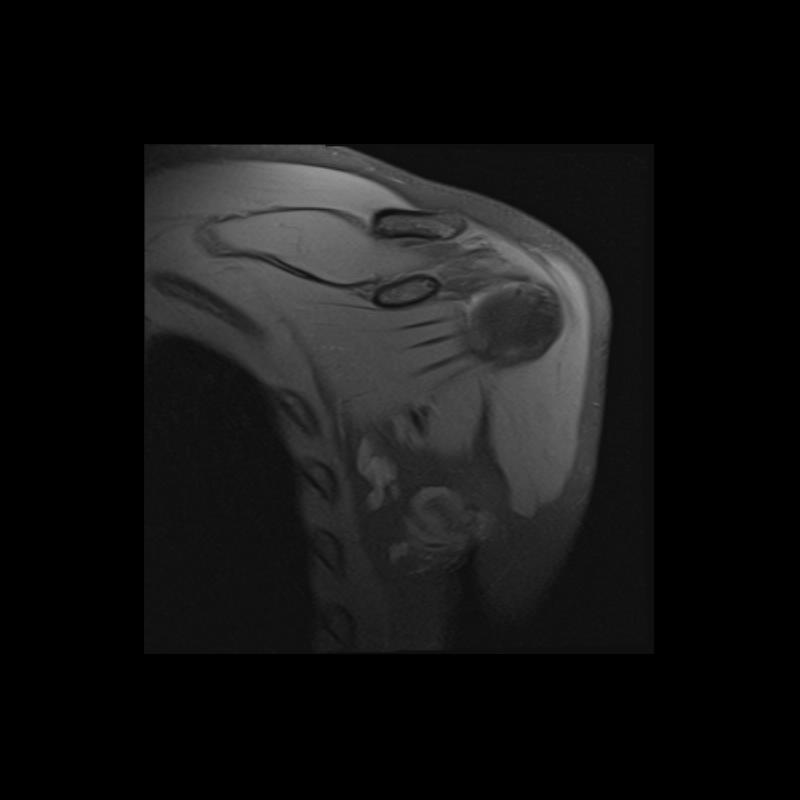

Shoulder MRI Anatomy